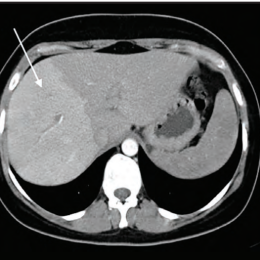

Pathologies veineuses et sinusoïdales du foie

Les maladies vasculaires du foie regroupent des atteintes des vaisseaux sanguins, veineux ou artériels, touchant à la fois la micro- et la macrocirculation hépatique. Ce dossier aborde spécifiquement les atteintes veineuses et sinusoïdales, des pathologies rares et souvent méconnues…